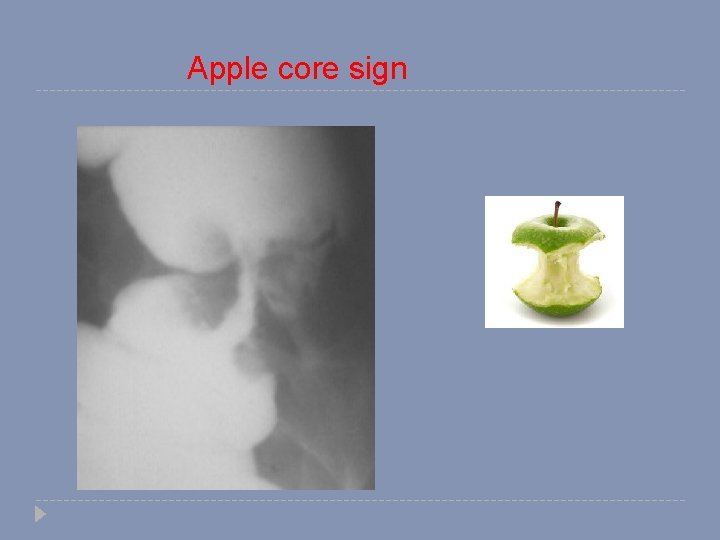

Abnormal study Colon Cancer (apple core sign)

Apple core sign